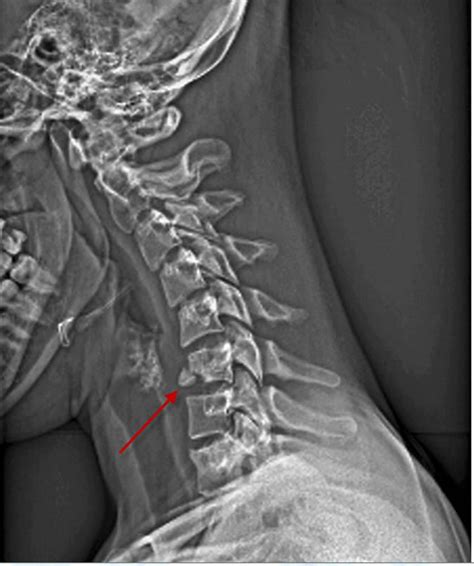

Cervical Insufficiency and Trauma: Insights Into Diagnosis and Management